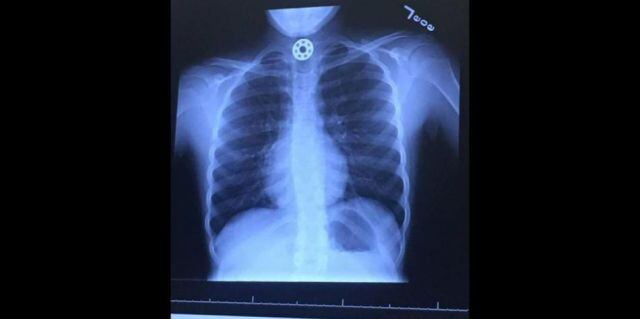

Britton aún podía hablar así que le explicó que se había tragado una de las tuercas de su Fidget Spinner. Completamente desesperada, Kelly llevó a su hija a urgencias, pero los médicos no pudieron descubrir si la pieza se había atorado en su esófago o en sus vías respiratorias.

Es así que tuvieron que conducirla hasta el hospital de niños de Texas. ‘El doctor estaba fascinado…esa misma mañana había conocido la existencia de los Spinners cuando estaba en el mall con su hijo, así que le sorprendió enfrentarse con un caso tan solo unas horas después’, contó Kelly.

Rápidamente le hicieron una tomografía y notaron que la tuerca estaba en su esófago. Para removerla, tuvieron que sedar a la niña y hacerle una endoscopía. Por suerte, Britton no se asfixió y logró sobrevivir.